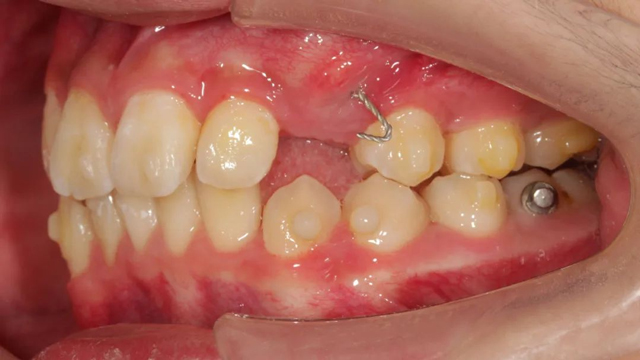

2021年8月(矫正前口内照)

这位小患者的口腔问题包括:牙列不齐,个别门牙反颌,左上尖牙完全埋伏阻生,另外,CBCT显示右上门牙牙根腭侧内还有一颗多生牙。

简单地说,牙齿不整齐只是小问题,他更大的问题是:在不该长牙的地方多长了一颗牙,而乳尖牙滞留,早该替换出来的尖牙长不出来,这两颗牙的问题如果不及时干预治疗,会带来很多长期的口腔问题。

据了解,位于腭侧的多生牙紧挨着已经替换完的1号恒牙(门牙),如不拔除会影响整个牙列的整齐度,后期也可能损伤1号牙的牙根,导致这颗牙齿松动甚至脱落。